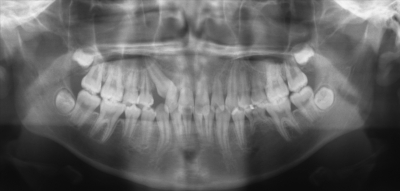

12歳の男児。上顎歯列の空隙を主訴として来院した。初診時の口腔内写真、エックス線写真及び矯正材料の写真を別に示す。上顎右側犬歯の歯冠近遠心幅径の予測値から、上顎のarchlength discrepancyは-2mmである。3⏌の開窓後、マルチブラケット装置を用いて非抜歯で治療を行うこととした。